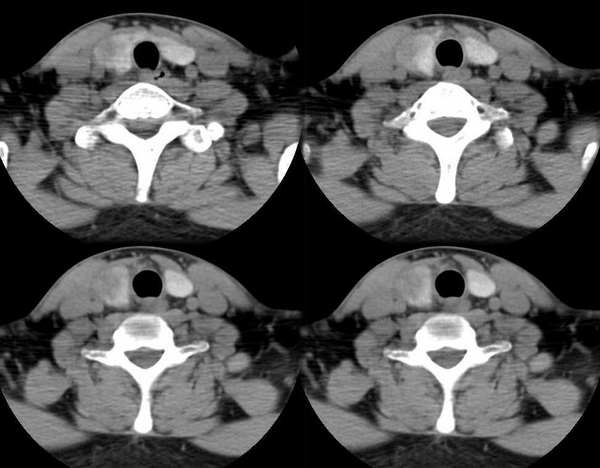

男,25岁,体温39.3度,发现右侧颈部包块.

平扫和增强病灶境界欠清、形状不规则,考虑甲状腺癌可能。

此病例特点:1、年轻男性,基本上是高热;2、右侧甲状腺肿大呈边界不清之低密度,但甲状腺境界清晰;3、基本没有增强但低密度的周边略呈边缘增强反应;4、最好补充病史:痛否?时间?(如痛、急性起病。)

据此,以甲状腺急性炎症可能性大。

甲状腺脓肿